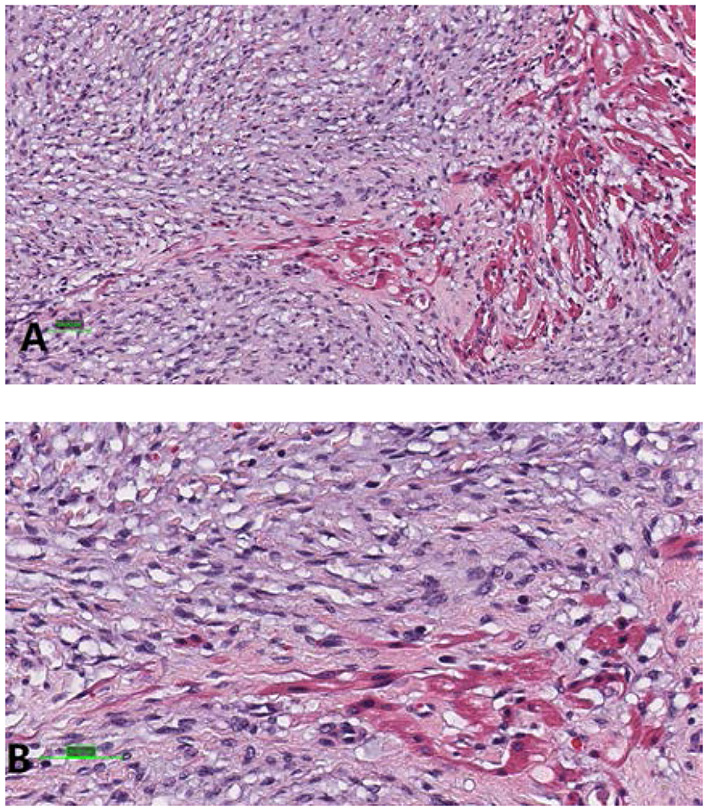

Figure 4

Examination under a light microscope (A); Magnification: 20x, and (B) 40x (hematoxylin and eosin staining).

The study protocol was approved by the Dalian Women and Children's Medical Center (Group) Institutional Ethics Committee. The legal guardian signed informed consent for the operation and clinical record review. The patient is a test-tube baby, which means that the baby was a result of in-vitro fertilization. Fetal cardiac uhrasonography showed solid mass occupying the right ventricular wall and pericardial effusion; therefore, the patient was transferred to Cardiac care unit (CCU) after birth, early vital signs were stable and physical examination showed no obvious abnormalities. Cardiac uhrasonography: A hypoechoic mass of about 36 mm × 23 mm on the right ventricular wall, narrowing of the right ventricular inflow tract (Figure 1), a small amount of pericardial effusion, patent foramen ovale (2 mm), and patent ductus arteriosus (2 mm). Cardiac CT angiography (CTA): An elliptical low-density shadow of 35 mm × 23 mm on the right ventricular wall, with the right ventricle compressed (Figures 2A,B). The patient gradually had shortness of breath, rapid heart rate and oliguria, and cardiac echocardiography indicated increased pericardial effusion during observation. Tumor excision and ligation of ductus arteriosus were performed on Day 6 after birth. During the operation, the tumor was found to be yellow and hard, with a clear boundary with the myocardial tissue. Part of the myocardial tissue was enlarged along the boundary between the tumor and the myocardial tissue, and the marginal myocardial tissue was cut from multiple locations for pathological examination to ensure complete tumor resection, the fibroma was completely removed (Figures 3A–C), and the right ventricular wall wound was directly sutured. After the first cardiopulmonary bypass, the patient had severe hypotension and hypoxemia, making the condition unsustainable. The cardiopulmonary bypass was arranged again; given severe damage to the right ventricular wall due to tumor excision, and right heart failure, the ductus arteriosus was opened, the foramen ovale was enlarged, and various vascular drugs such as dopamine, adrenaline and prostaglandin were given; the patient was barely out of cardiopulmonary bypass, and transferred to the ICU with delayed sternal closure. The patient's vital signs were gradually stable, the chest was closed on Day 3, the respirator was removed on Day 6, and the patient was discharged on Day 14 after an operation. At present, the heart function has returned to normal, with a satisfactory prognosis. Pathologic results confirmed the presence of fibroma (Figures 4A,B).